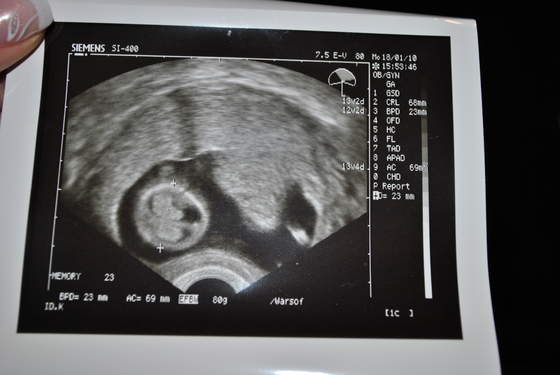

Dzidziolek rośnie ma 2,55 cm, co wg usg potwierdza 9w3d (wiec ciąża trochę młodsza ze względu na późną owulacje- termin zostawiam bez zmian bo i tak będzie sie zmieniał)Serduszko bije 163/min .